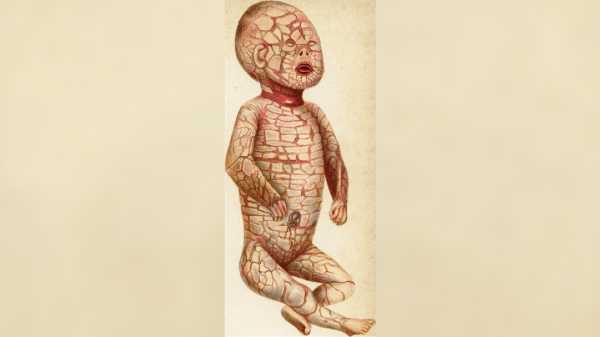

Рідкісне генетичне захворювання, яке призводить до появи твердої «луски» у немовлят

Рідкісне генетичне захворювання, яке призводить до появи твердої «луски» у немовлят